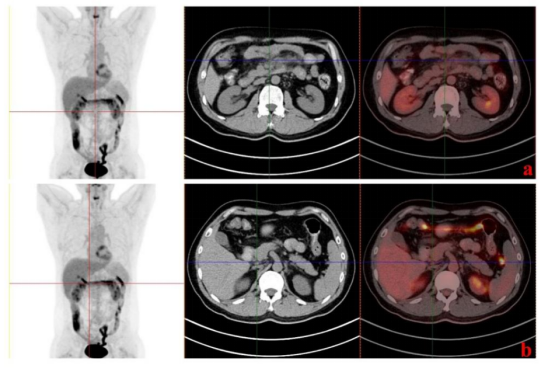

此外,我们检测CD4+/CD8+T细胞的比例发现其在第60天下降后增加,而CAR拷贝数先增加后减少。我们推测,肿瘤可能在第60天左右复发,休眠的CAR-T细胞被激活,导致CAR拷贝数升高,细胞毒性CD8+ T细胞增殖并杀死肿瘤,第四个月PET-CT(图5)提示患者已完全缓解(CR)。

图5. 输注后4个月PET-CT检测